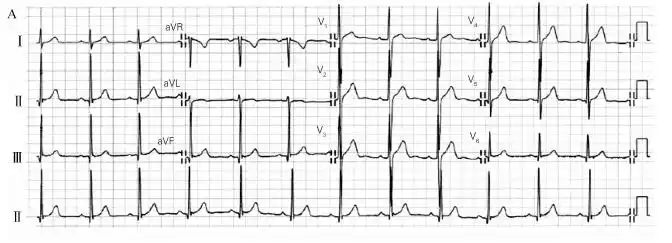

右室肥厚心电图诊断新视点